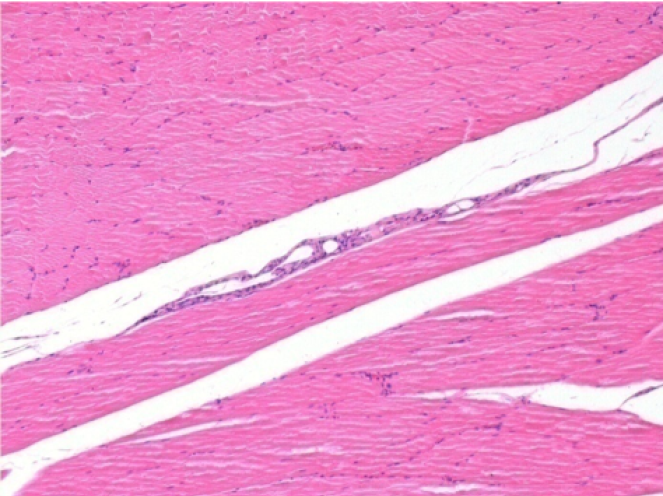

Через 1 місяць після ін'єкції Ендопілу 0,1 мл у правий претибіальний м'яз.

Те, що видно на знімках чорним кольором, не є некрозом, як можуть собі уявити деякі науковці!

Насправді, слід взяти до уваги 4 висновки

Через 3 місяці (90 днів) після ін'єкції Ендопіл 0,1 мл в правий претибіальний м'яз.